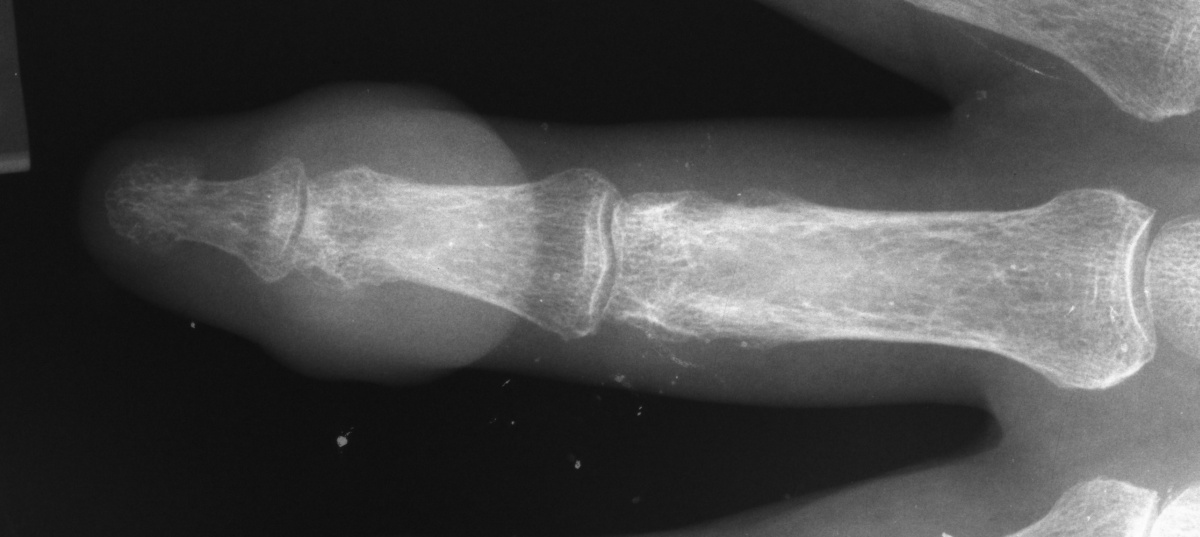

| Xrays showed a homogeneous

shadow consistent with a large gouty tophus. |